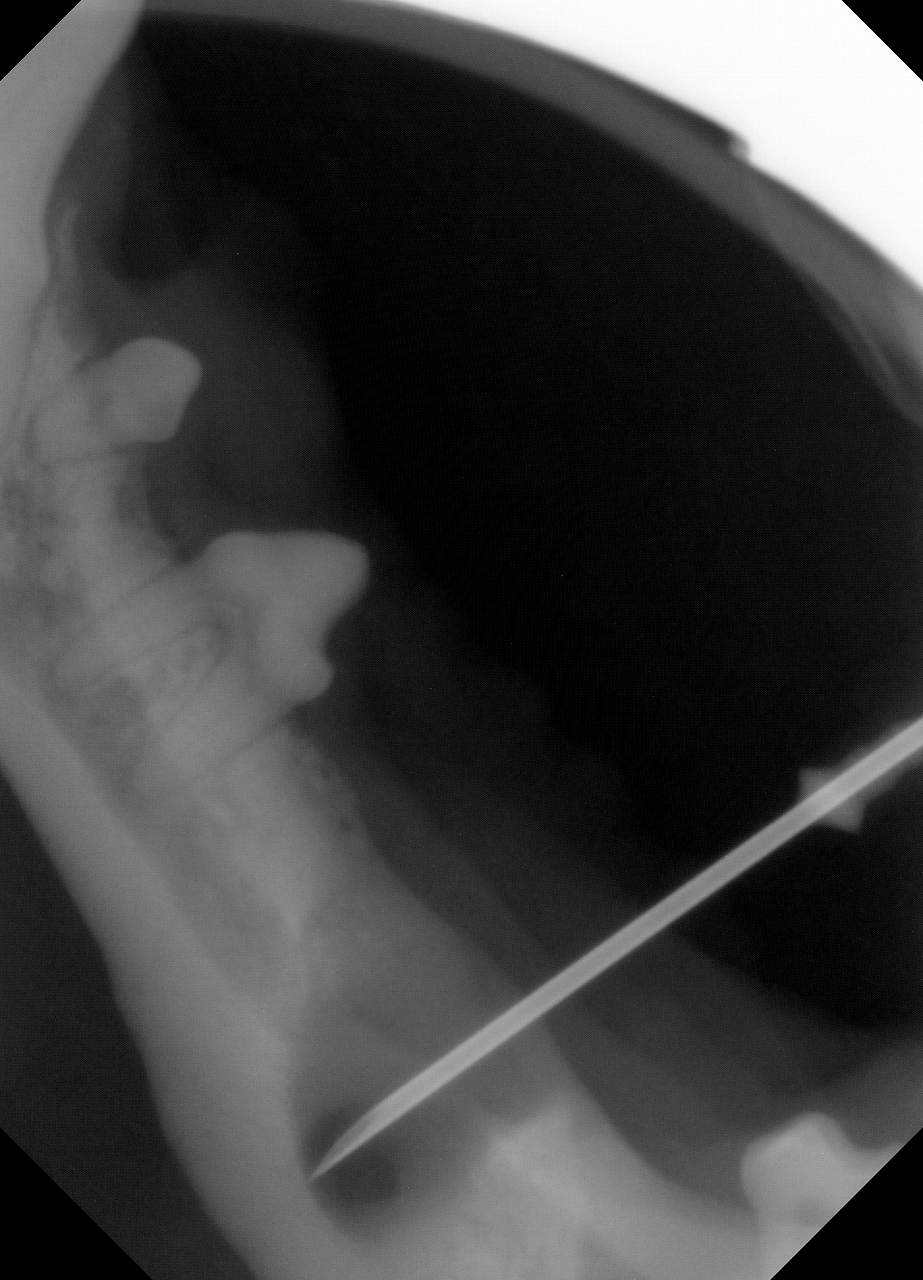

その次に歯科用レントゲンで歯とアゴの骨のレントゲンを撮影してみたところ......

病変部を切開して内部の洗浄と抗生物質を注入し、粘膜を縫合して終了としました。

後から飼主様に確認すると、歯科処置までの間に自宅で臼歯が一本抜けていたことがわかりました。